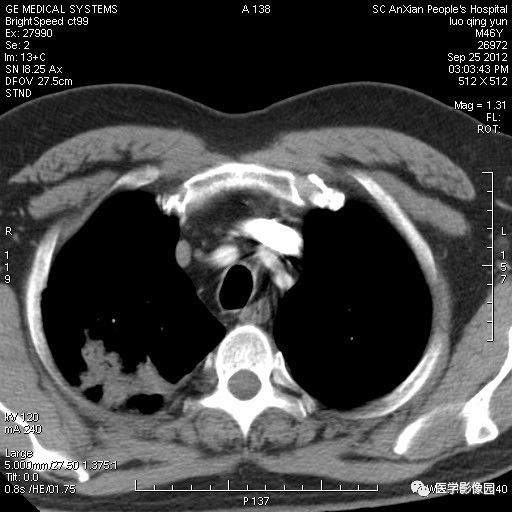

影像学表现:右上肺见不规则团块状高密度阴影,略有分叶级毛刺,边缘模糊,邻近胸膜增厚,增强扫描呈轻中度强化。

诊断结果:右上肺炎性假瘤

本病影像学表现无绝对特征性。单发多见,多位于肺表浅部位,多呈圆形或椭圆形,直径多在2-5cm或更大;多有假包膜,边缘多清晰光整,有时也毛糙,并可有分叶或毛刺;邻近胸膜局限性增厚、牵拉,病灶边缘呈桃尖样突起即桃尖征(尖端指向胸膜);增强扫描多呈中度均匀强化,持续时间较长。亦可显著强化。